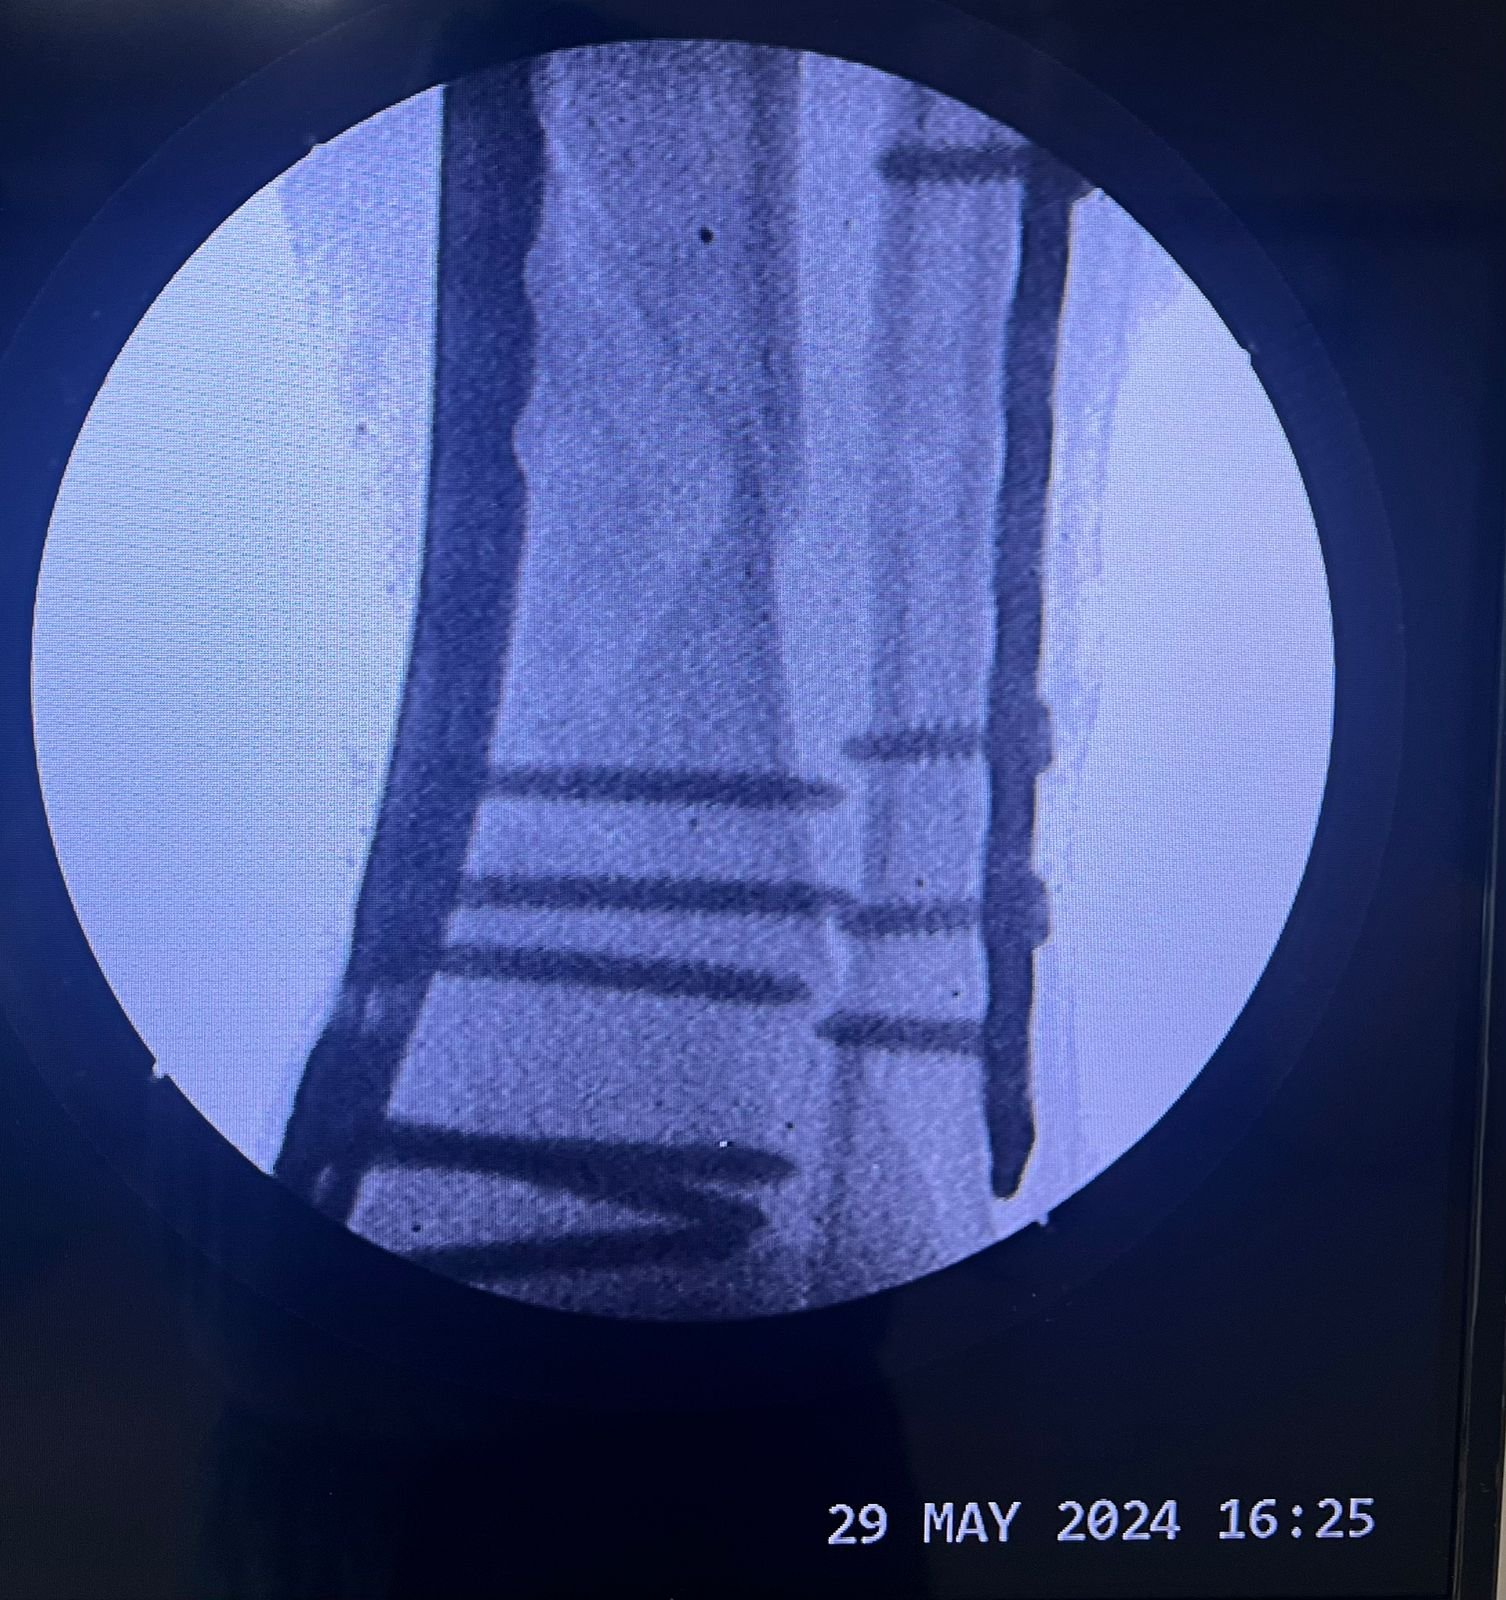

Pre op & postop X-ray compound fracture lower tibia

& fibula | Heal fracture pre & postop | Clavicle